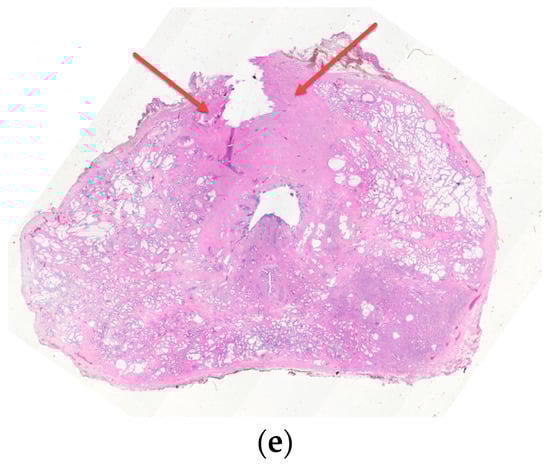

10. Prostatic Abscess